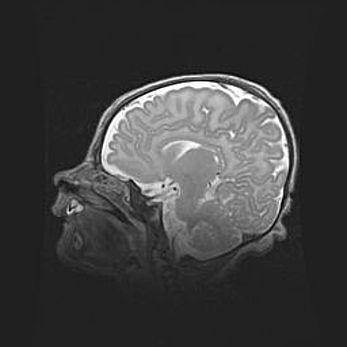

Лейкомаляция с кистозно-глиозной дегенерацией головного мозга.

Возраст: 2 месяца 25 дней

Вес: 6400 г

Окружность головы: 40 см

Срок гестации: 41 неделя

Лейкомаляцию относят к ишемически-гипоксическим повреждениям головного мозга, диагностируемым у новорожденных. При лейкомаляции в головном мозге обнаруживают очаги некроза, возникшие после тяжелой гипоксии и нарушения кровотока. В процессе морфогенеза очаги проходят три стадии: 1) развития некроза, 2) резорбции и 3) формирования глиозного рубца или кисты. Перивентрикулярная лейкомаляция (ПЛ) встречается примерно в 12% случаев среди новорожденных, обычно – у недоношенных детей, причем, частота ее зависит от массы, с которой младенец появился на свет. Наибольшее число малышей страдает лейкомаляцией, если масса при рождении 1500-2500 г.